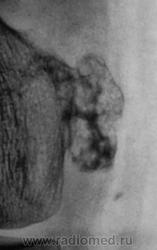

Грибовидная солитарная остеохондрома бедра у 28-летнего мужчины. Оперативное и гистологическое подтверждение диагноза.(Рейнберг).

Определяется "грибовидное" образование на ножке с мелкобугристой поверхностью, крупинчатым пятнистым рисунком,обусловленым наличием костных островков, веерообразных пучков и перегородок лежащих на светлом фоне хряща

Остеохондрома.